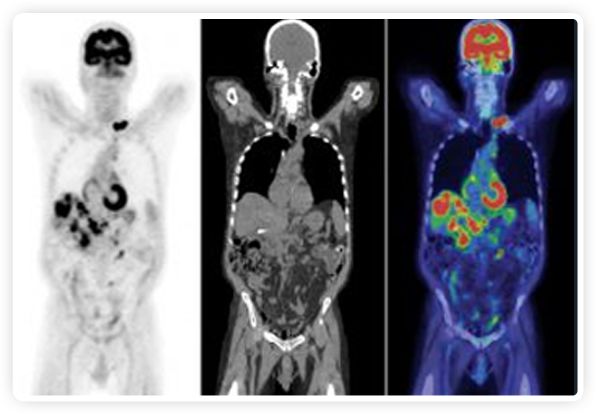

提起放療設備的引導系統,大家通常會想到結構性成像的CT或核磁。但你有沒有想過用功能性成像來引導放療呢?美國的一家醫(yī)療器械公司從2011年就致力于研究開發(fā)用PET提供生物學指導放射治療的設備BgRT。BgRT能實時利用癌癥的生物學特征作為信號指導治療全身腫瘤。

正電子發(fā)射斷層掃描(PET)是癌癥檢測中已建立的成像標準,與其他成像方式相比,PET能提供高靈敏度和特異性的圖像。

到目前為止,放射腫瘤學中(使用的圖像主要是結構性的,而PET圖像可以提供生物學信息。通過使用注射示蹤劑,例如18-FDG,PET可以描繪腫瘤的代謝活性,使其“點亮”。(FDG是用于可視化癌癥代謝的最廣泛使用的示蹤劑。與正常組織相比,腫瘤細胞保留更高水平的FDG。)不同的PET示蹤劑可以識別腫瘤的不同生物學特征,例如特定生物標志物抗原(例如,PSMA)或甚至探測免疫系統本身(例如,PDL1表達或活化的T細胞)。

RefleXion將PET成像與立體定向放射治療相結合。在注射示蹤劑后,RefleXion的技術基于示蹤劑信號實時地在一個或多個目標上引導治療性X射線。使用這種專有方法,RefleXion的平臺有可能比現有系統向癌癥病變提供更高劑量的輻射,并改善周圍健康組織的保護。